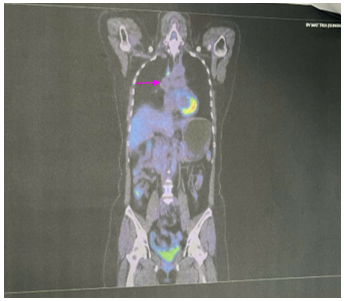

Đánh giá sau 06 chu kỳ Pemetrexed – Carboplatin – Pembrolizumab

PET CT: Hình ảnh nốt mờ bờ tua gai vùng đỉnh phổi phải kích thước 9x12mm; không tăng chuyển hóa FDG. Hạch cạnh khí quản đoạn thấp kích thước 7x9mm, tăng chuyển hóa FDG (SUV max: 4.83). Chưa phát hiện hình ảnh tăng chuyển hóa FDG khu trú, bất thường tại các vị trí khác trên PET CT toàn thân

Hình 8: Hình ảnh PET CT:  Hạch cạnh khí quản đoạn thấp kích thước 7x9mm, tăng chuyển hóa FDG (SUV max: 4.83). (mũi tên màu hồng)

Sau 6 chu kỳ Pemetrexed – Carboplatin– Pembrolizumab, đánh giá bệnh đáp ứng;bệnh nhân tiếp tục duy trì Pemetrexed – Pembrolizumab.